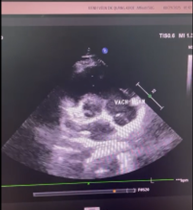

Hình ảnh Giant Eustachian Valve di chuyển trong buồng tâm nhĩ phải trên siêu âm tim của Chị Nguyễn T. V (mũi tên)

👉 Trong quá trình tầm soát, bác sĩ phát hiện chị mắc phải một dị tật bẩm sinh cực hiếm gặp trong buồng tâm nhĩ phải của quả tim, chỉ chiếm khoảng 0,2 % dân số thế giới – Quá phát van Eustachian (Giant Eustachian valve).